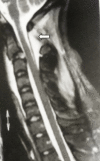

To describe the biomechanically relevant anatomy of the Axis vertebra and the load transfer patterns within the bone, and on that basis, to postulate its mechanism of injury, a literature review was conducted of the anatomy and biomechanics of Axis fractures. Two hypotheses have been presented: the internal gear hypothesis and the leaf spring hypothesis. Both are based on the trabecular anatomy of the vertebra and its load transmission patterns. The relationship of the Axis with Hangman's injury is also discussed. According to the leaf spring hypothesis, the C2 pedicle corresponds to the shackle in the assembly and constitutes the weak link. The trabecular architecture of the Axis is such that the primary compression of the trabeculae is directed from the superior facet to the C2-3 endplate, with few trabeculae directed to the inferior facet. Along with the trabecular void in this area, this renders the isthmus vulnerable to trauma. The isthmus of the Axis is biomechanically susceptible to injury due to its unique anatomy in relation to the whole cervical spine and the internal load transmission patterns of the bone. The author suggests that in the flexion type of Hangman's injury, the C1-2 posterior ligaments are disrupted and need to be addressed.